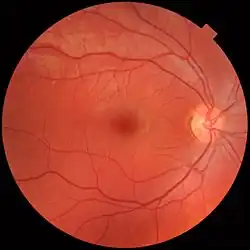

Three types of cells in the retina convert light energy into electrical energy used by the nervous system: rods respond to low intensity light and contribute to perception of low-resolution, black-and-white images; cones respond to high intensity light and contribute to perception of high-resolution, coloured images; and the recently discovered photosensitive ganglion cells respond to a full range of light intensities and contribute to adjusting the amount of light reaching the retina, to regulating and suppressing the hormone melatonin, and to entraining circadian rhythm.[1]

About 15° temporal and 1.5° below the horizontal is the blind spot created by the optic nerve nasally, which is roughly 7.5° high and 5.5° wide.[18]

Macular degeneration is especially prevalent in the U.S. and affects roughly 1.75 million Americans each year.[105] Having lower levels of lutein and zeaxanthin within the macula may be associated with an increase in the risk of age-related macular degeneration.[106] Lutein and zeaxanthin act as antioxidants that protect the retina and macula from oxidative damage from high-energy light waves.[107] As the light waves enter the eye, they excite electrons that can cause harm to the cells in the eye, but they can cause oxidative damage that may lead to macular degeneration or cataracts. Lutein and zeaxanthin bind to the electron free radical and are reduced rendering the electron safe. There are many ways to ensure a diet rich in lutein and zeaxanthin, the best of which is to eat dark green vegetables including kale, spinach, broccoli and turnip greens. Nutrition is an important aspect of the ability to achieve and maintain proper eye health. Lutein and zeaxanthin are two major carotenoids, found in the macula of the eye, that are being researched to identify their role in the pathogenesis of eye disorders such as age-related macular degeneration and cataracts.[108]